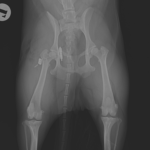

股関節脱臼に対するBUSTOR #67

輪禍外傷による股関節脱臼の患者さんに対してBullet–Shaped Toggle Rod (BUSTOR)で整復を行いました。本症例は恥骨の骨折も併発していたため、CTで寛骨臼の評価も実施しました。低侵襲かつ短時間で整復が可能です。しばらくは安静が必要です。